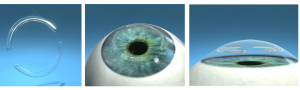

1) O que é e qual objetivo do Segmento de Anel (anel intra estromal)?

O anel intracorneano (Kerarings ®, Anel de Ferrara ® ou Intacs ®) é uma órtese transparente composto de um material inerte e biocompatível ao olho, de formato semicircular, de espessuras e diâmetro variáveis.

O objetivo do anel é regularizar e diminuir a curvatura corneana, e consequentemente melhorar a visão. Além disso, esse dispositivo é capaz de diminuir ou corrigir os erros de refração da Córnea de um paciente com Ceratocone.

A melhor indicação de tratamento com uso do anel corneano é no estágio moderado do Ceratocone, pois tem como objetivo tentar melhorar a estrutura da córnea e regularizar as deformações corneana, e tentar corrigir ou diminuir os erros de grau associados a esta córnea. O anel intracorneano é fabricado a partir do PMMA (polimetilmetacrilato), material comprovadamente inerte, biocompatível, não havendo risco de rejeição, pois este material é utilizado há décadas na fabricação de implantes intra-oculares.

Em seguida, acontece o implante de 1 ou 2 seguimentos de anel. A cirurgia dura em média 30 minutos. Os segmentos vão tentar o aplanamento do ápice da córnea tentando deixá-la o mais próximo do natural. Esta técnica é reversível, sem danos para a córnea, e não é uma técnica refrativa, ou seja, o paciente deverá utilizar óculos ou lente de contato após a cirurgia de Ceratocone.